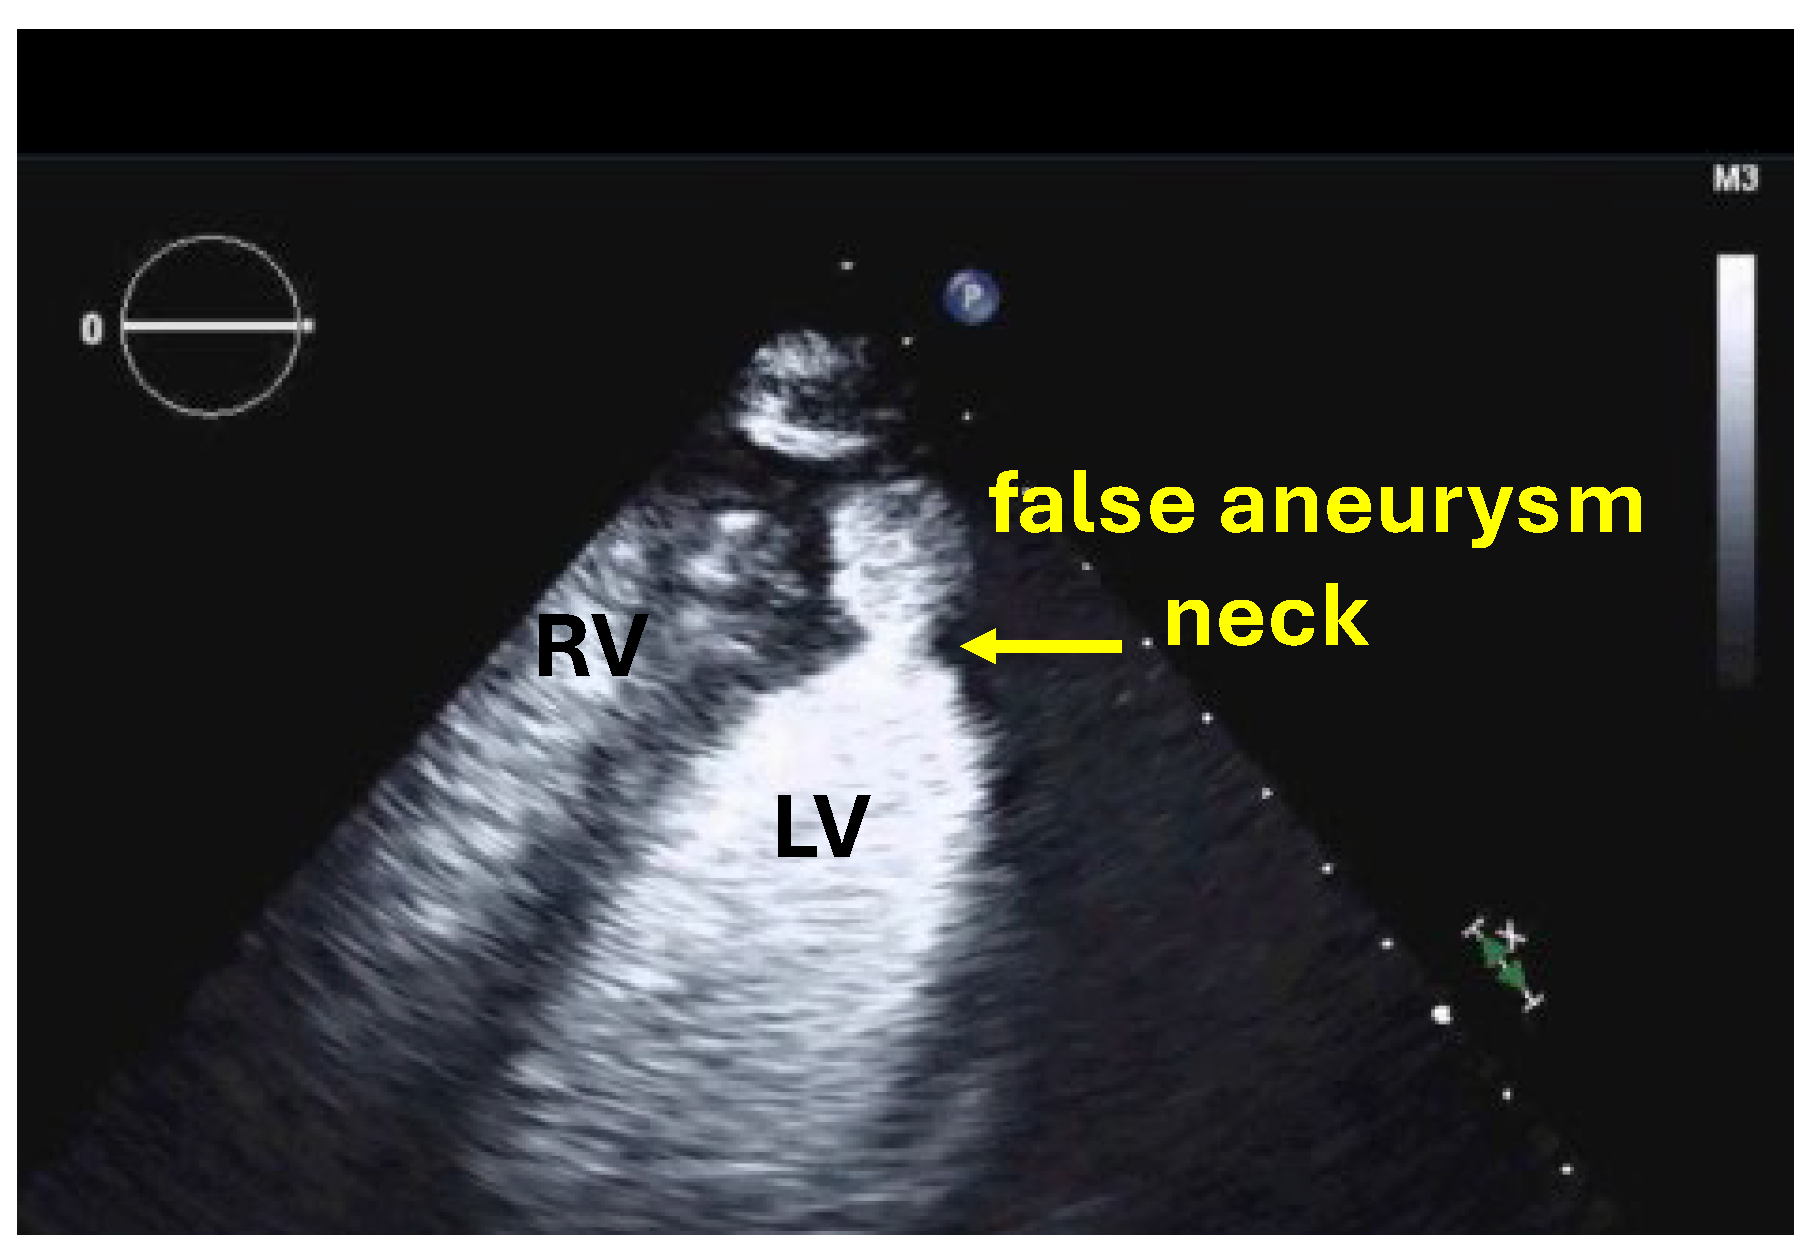

| Pseudoaneurysm |

| Typical findings | Clear demarcation from the normal myocardium Narrow neck of false aneurysms Search for associated thrombi and pericardial effusion (more likely near false aneurysms) |

| Alternative imaging | Cardiac MRI or cardiac CT in patients with contraindications to UEAs or inadequate recordings with UEAs |